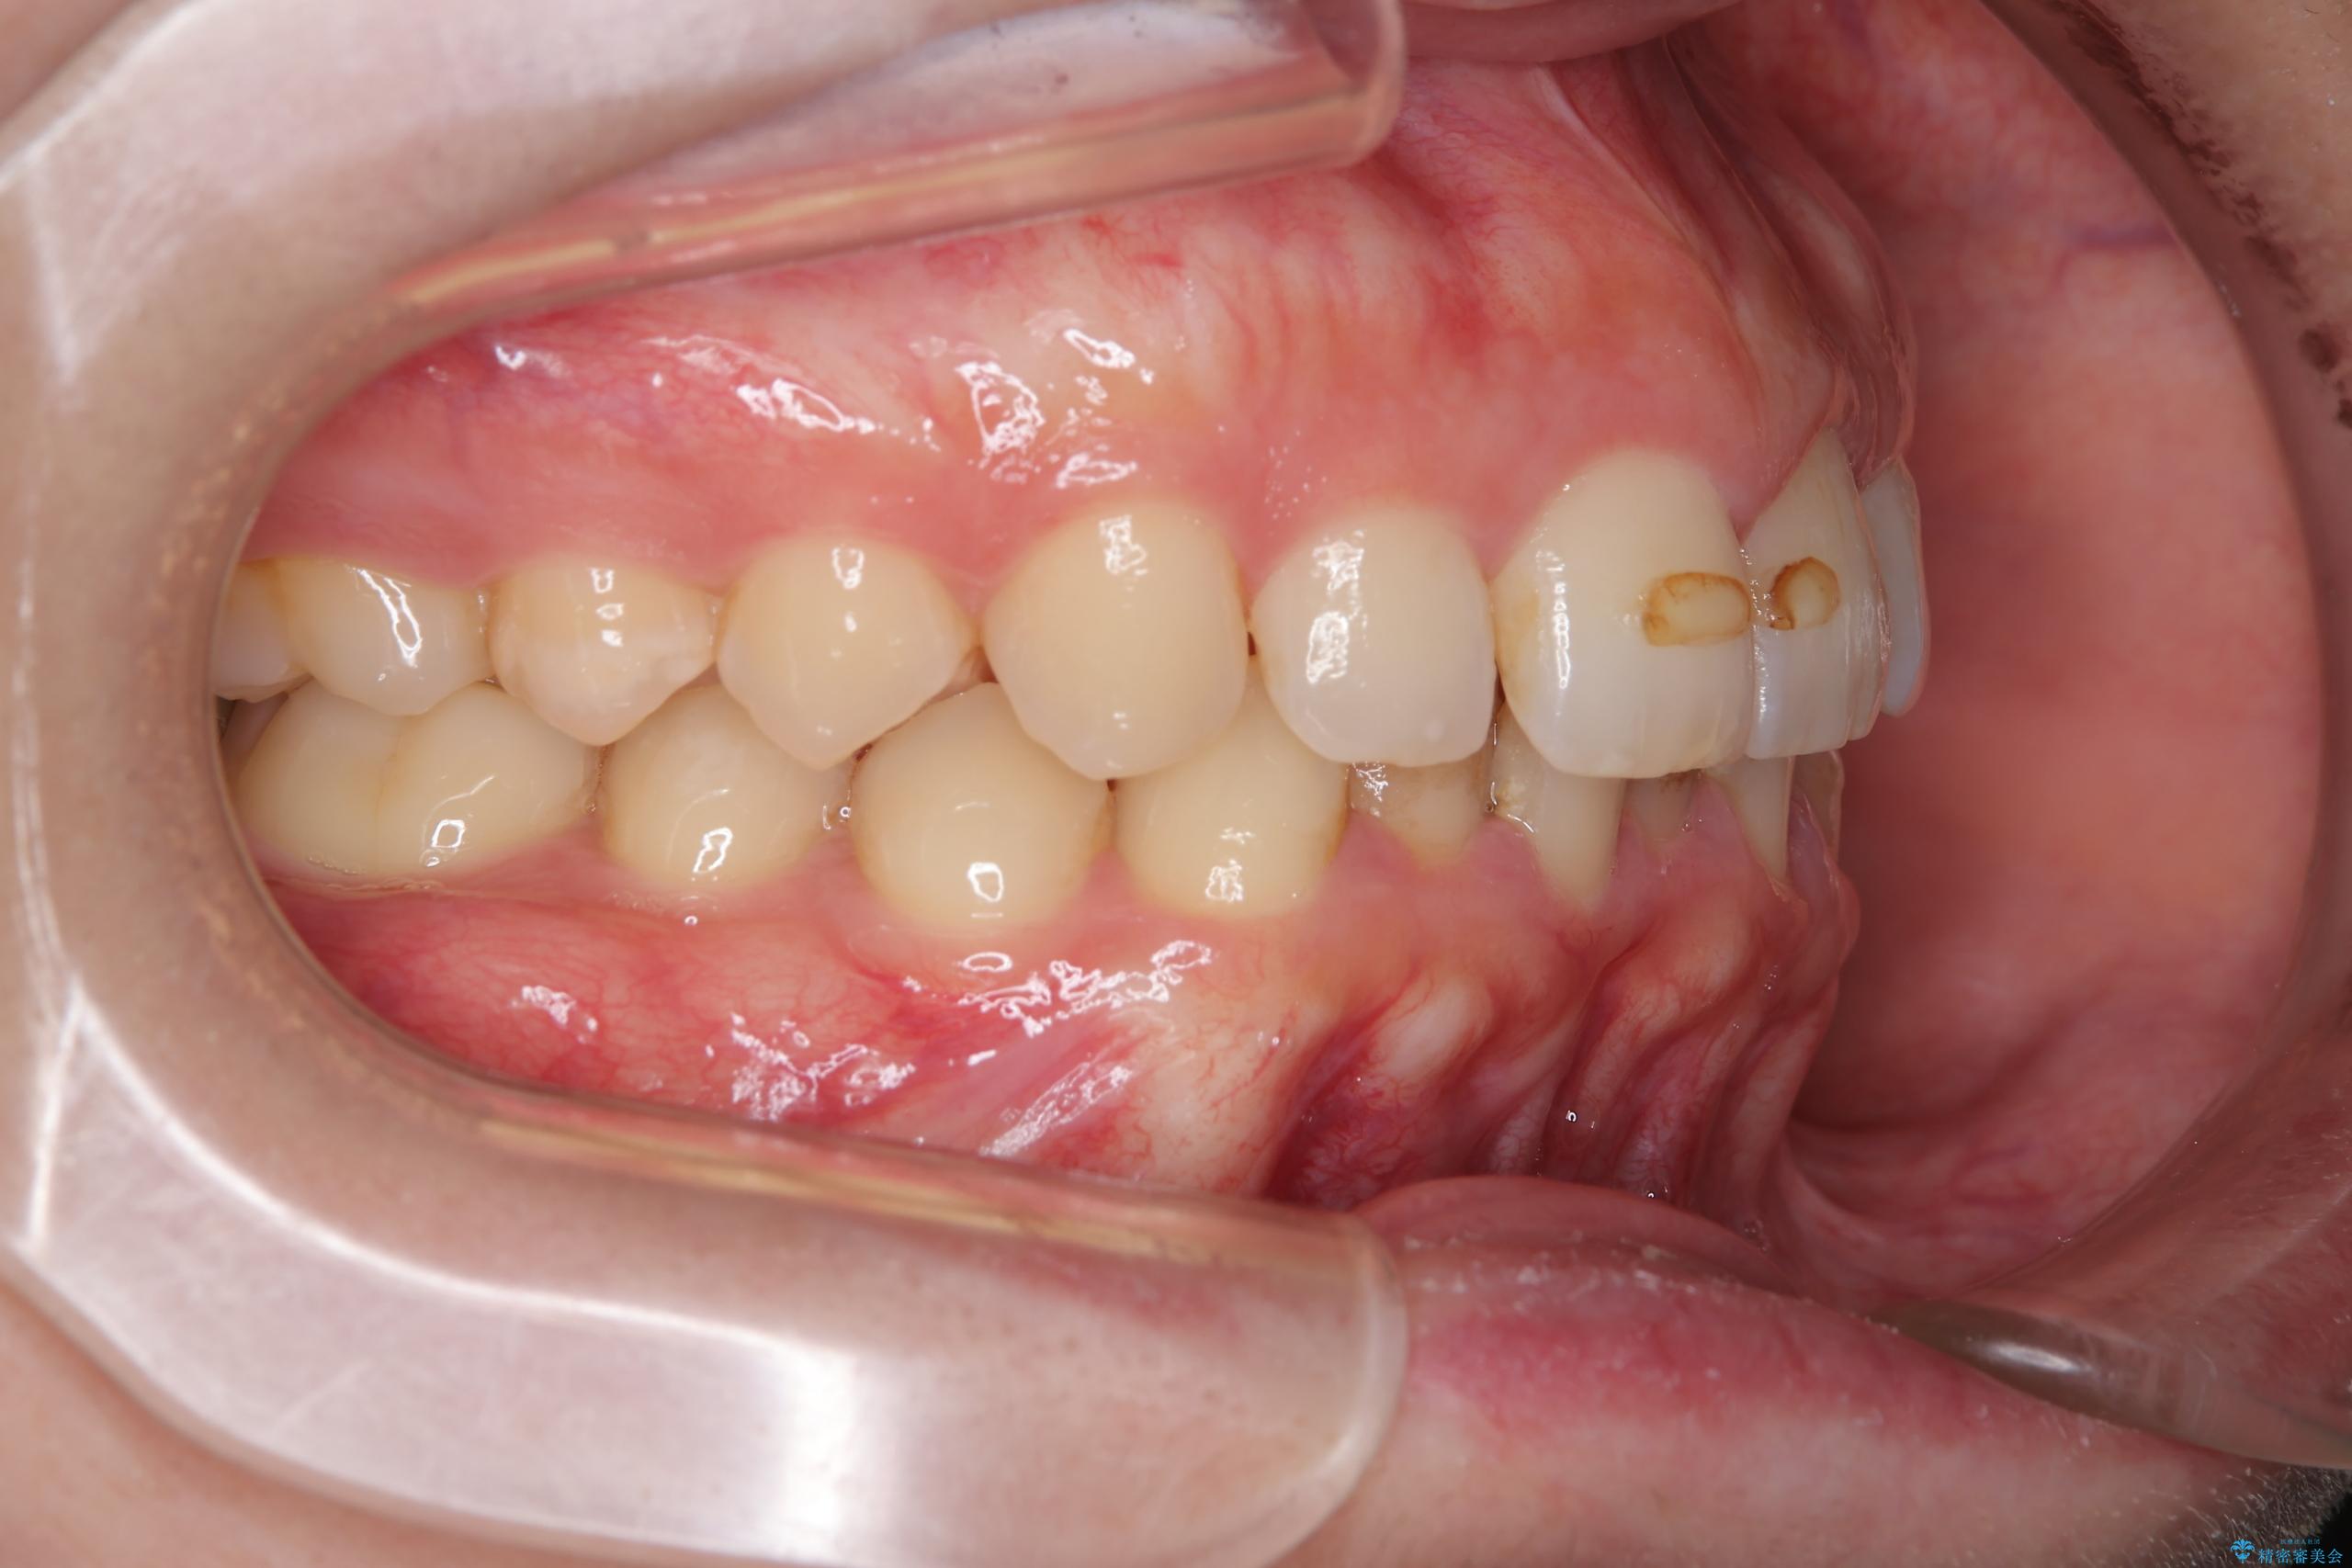

右側臼歯部の咬合改善のために、臼歯部のみ部分的なワイヤー矯正を行い、咬合改善がみられてからインビザラインにて全体的な矯正を行なっていく治療計画を立てました。

噛み合わせをよくするために、ワイヤー矯正とインビザライン矯正のどちらの期間も必要な箇所にゴム掛けを行いながら治療を行いました。